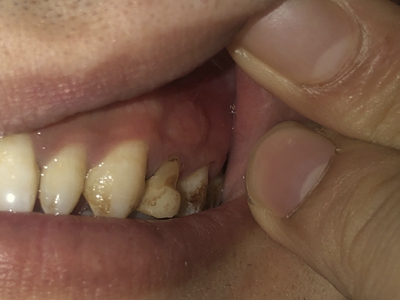

楔状缺损与年龄相关,即年龄越大,缺损越重,患者多有横刷牙习惯,患牙为多颗甚至全口,常以口角附近的牙齿(尖牙、前磨牙)为重。典型表现为牙颈部缺损,呈楔形,由两个夹面组成,口大底小,缺损处质地坚硬,表面光滑,边缘整齐,无染色,轻微泛黄常为牙齿本色,严重时可导致牙髓腔暴露甚至牙齿横向折断,根据缺损深浅不同,可伴有牙齿敏感甚至疼痛。

不正确的刷牙方法,尤其是横刷法是发生楔状缺损的主要原因,因为牙颈部结构比较薄弱,易发生磨损。另外,颊面牙颈部是咬合应力集中区,长期的咀嚼压力使牙体组织疲劳,应力集中区出现破坏,也会造成楔状缺损。龈沟内酸性渗出物,也与楔状缺损的发生有关。